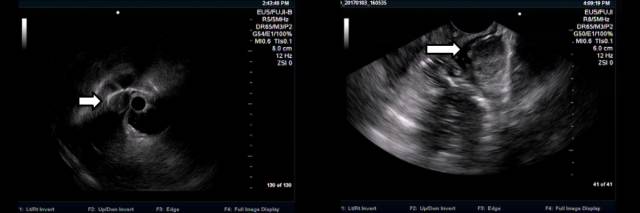

下面患者在外院胃镜和CT(图 A-B)均考虑胃底粘膜下肿瘤,拟双镜联合切除。

术前来我院完善超声内镜检查提示肝左叶近膈顶血管瘤(图A-B)

图A:环扫EUS提示肝脏近膈顶类圆形血管瘤(白色箭头);图B:线阵EUS见病灶上方的固有肌层完整(白色箭头)